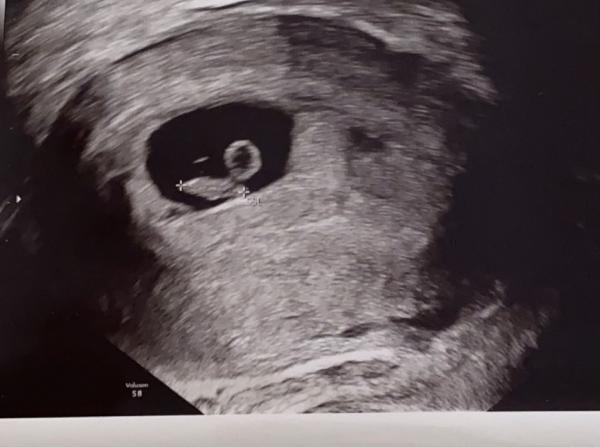

Hallo  ich bin jetzt bei 13+2 Habe hier ein Bild von 7+4 mich interessiert was die ramzi Methode sagt. Mein bauchgefühl ist Mädchen. Wenn wer es erkennt gerne schreiben ☺️ Ist aktuell die 3 Schwangerschaft  Bild 1 ist aktuelle (7+4) Bild 2 ist 2 Schwangerschaft ist ein Mädchen (6+1) Bild 3 ist 3 Schwangerschaft ist ein Junge (6+4)